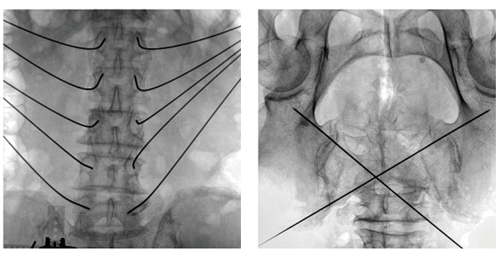

Description: Male, 45 years old

Surgery: Spinal tumor separation with T2,T4 pedicle screw fixation

Numbers of screws: 4